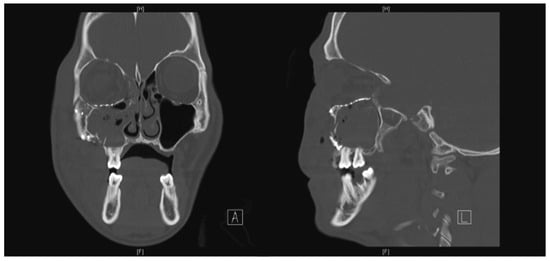

The surgery took place 10 days following the accident due to neurosurgical concerns regarding his brain injury. Intraoperatively, the periorbita surrounding the herniated contents was noted to be disrupted. A 0.4-mm titanium curved plate was used to reconstruct the orbital rim, and the medium 0.4-mm precontoured titanium orbital plate (Figure 2) was used for reconstruction of the orbital floor defect (DePuy Synthes, Johnson & Johnson, Solothurn, Switzerland). Intraoperatively, he had a negative forced-duction test and postoperatively, he was noted to have full range of extraocular movements of his right eye. The postoperative CT scan demonstrated anatomical placement of the orbital floor plate with reduction of all periorbita (Figure 3).

Figure 3. Coronal and sagittal cuts of the postoperative CT scan of the face (Case 1) demonstrating reduction of all periorbita.